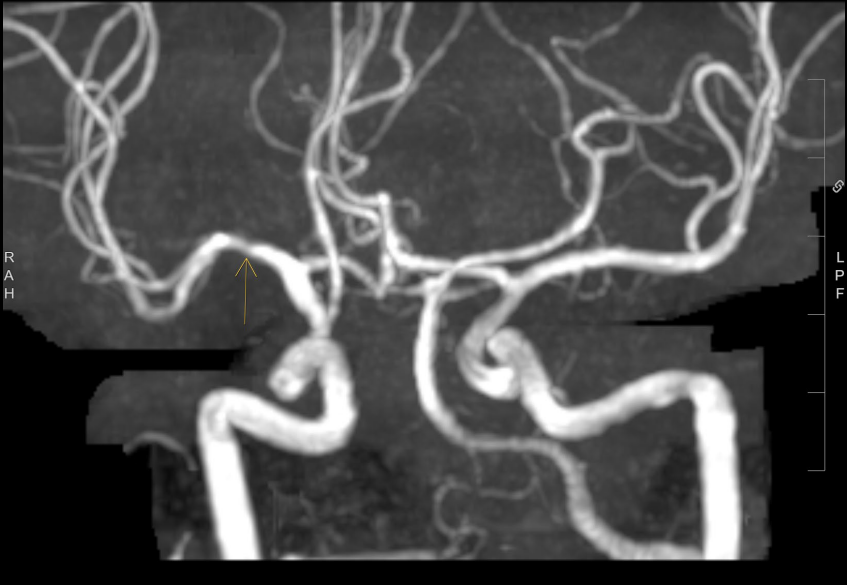

Query for the neurologists. Healthy 37-year-old male. Incidental asymptomatic right middle cerebral artery stenosis noted on a Prenuvo scan. What is your recommendation?

@Brandon_Beaber perfusion study and vessel wall. Optimize risk factors. Are there any ischemic lesions on the right MCA territory?